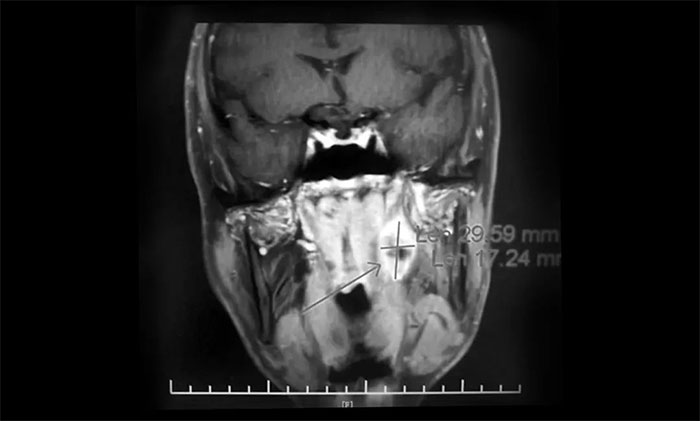

一位64歲男性患者,因“左頸部淋巴結腫大伴鼻出血半月”在外院行鼻咽鏡活檢病理結合影像學檢查,提示鼻咽癌可能。為尋求進一步治療近期來到我院。查MRI:左側鼻咽部實性佔位性病變,考慮惡性腫瘤,侵及左側咽旁間隙;左側下頜腺區及頸部淋巴結異常腫大(轉移可能)。

▲ 入院MRI影像